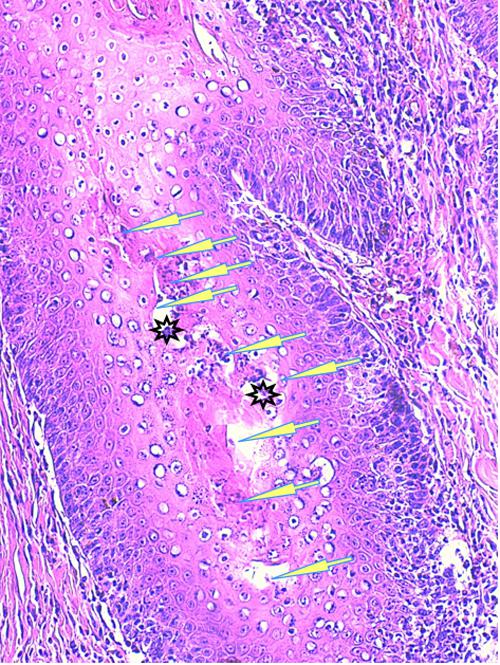

Photo 1 (Hémalun Eosine X 40) peau velue: L’épiderme et les infundibula folliculaires

sont hyperplasiques et hyperkératosiques. Les infundibula folliculaires sont le siège de pustules luminales et

pariétales, avec des fissurations linéaires parallèles au grand axe des follicules.

Le derme montre un inflammation péri-vasculaire et folliculo-centrée à diffuse.

Légendes de la Photo 1 :

- Double flèche bleue pointillée : grand axe des infundibula folliculaires à gaine épithéliale hyperplasique

- Double flèche verte : derme

- Ovales jaunes : pustules dans la paroi des follicules pileux

- Flèches jaunes : fissures linéaires dans la paroi des follicules pileux qui sont parallèles au grand axe des infundibula folliculaires

- Étoiles vertes évidées : lumière d’un follicule pileux hyperkératosique occupée par de la kératine et couche cornée hyperkératosique

- Étoiles rouges pleines : infiltrat dermique périvasculaire, périannexiel à diffus

- Étoiles turquoises pleines : lumière de follicules pileux obstruée de débris inflammatoires